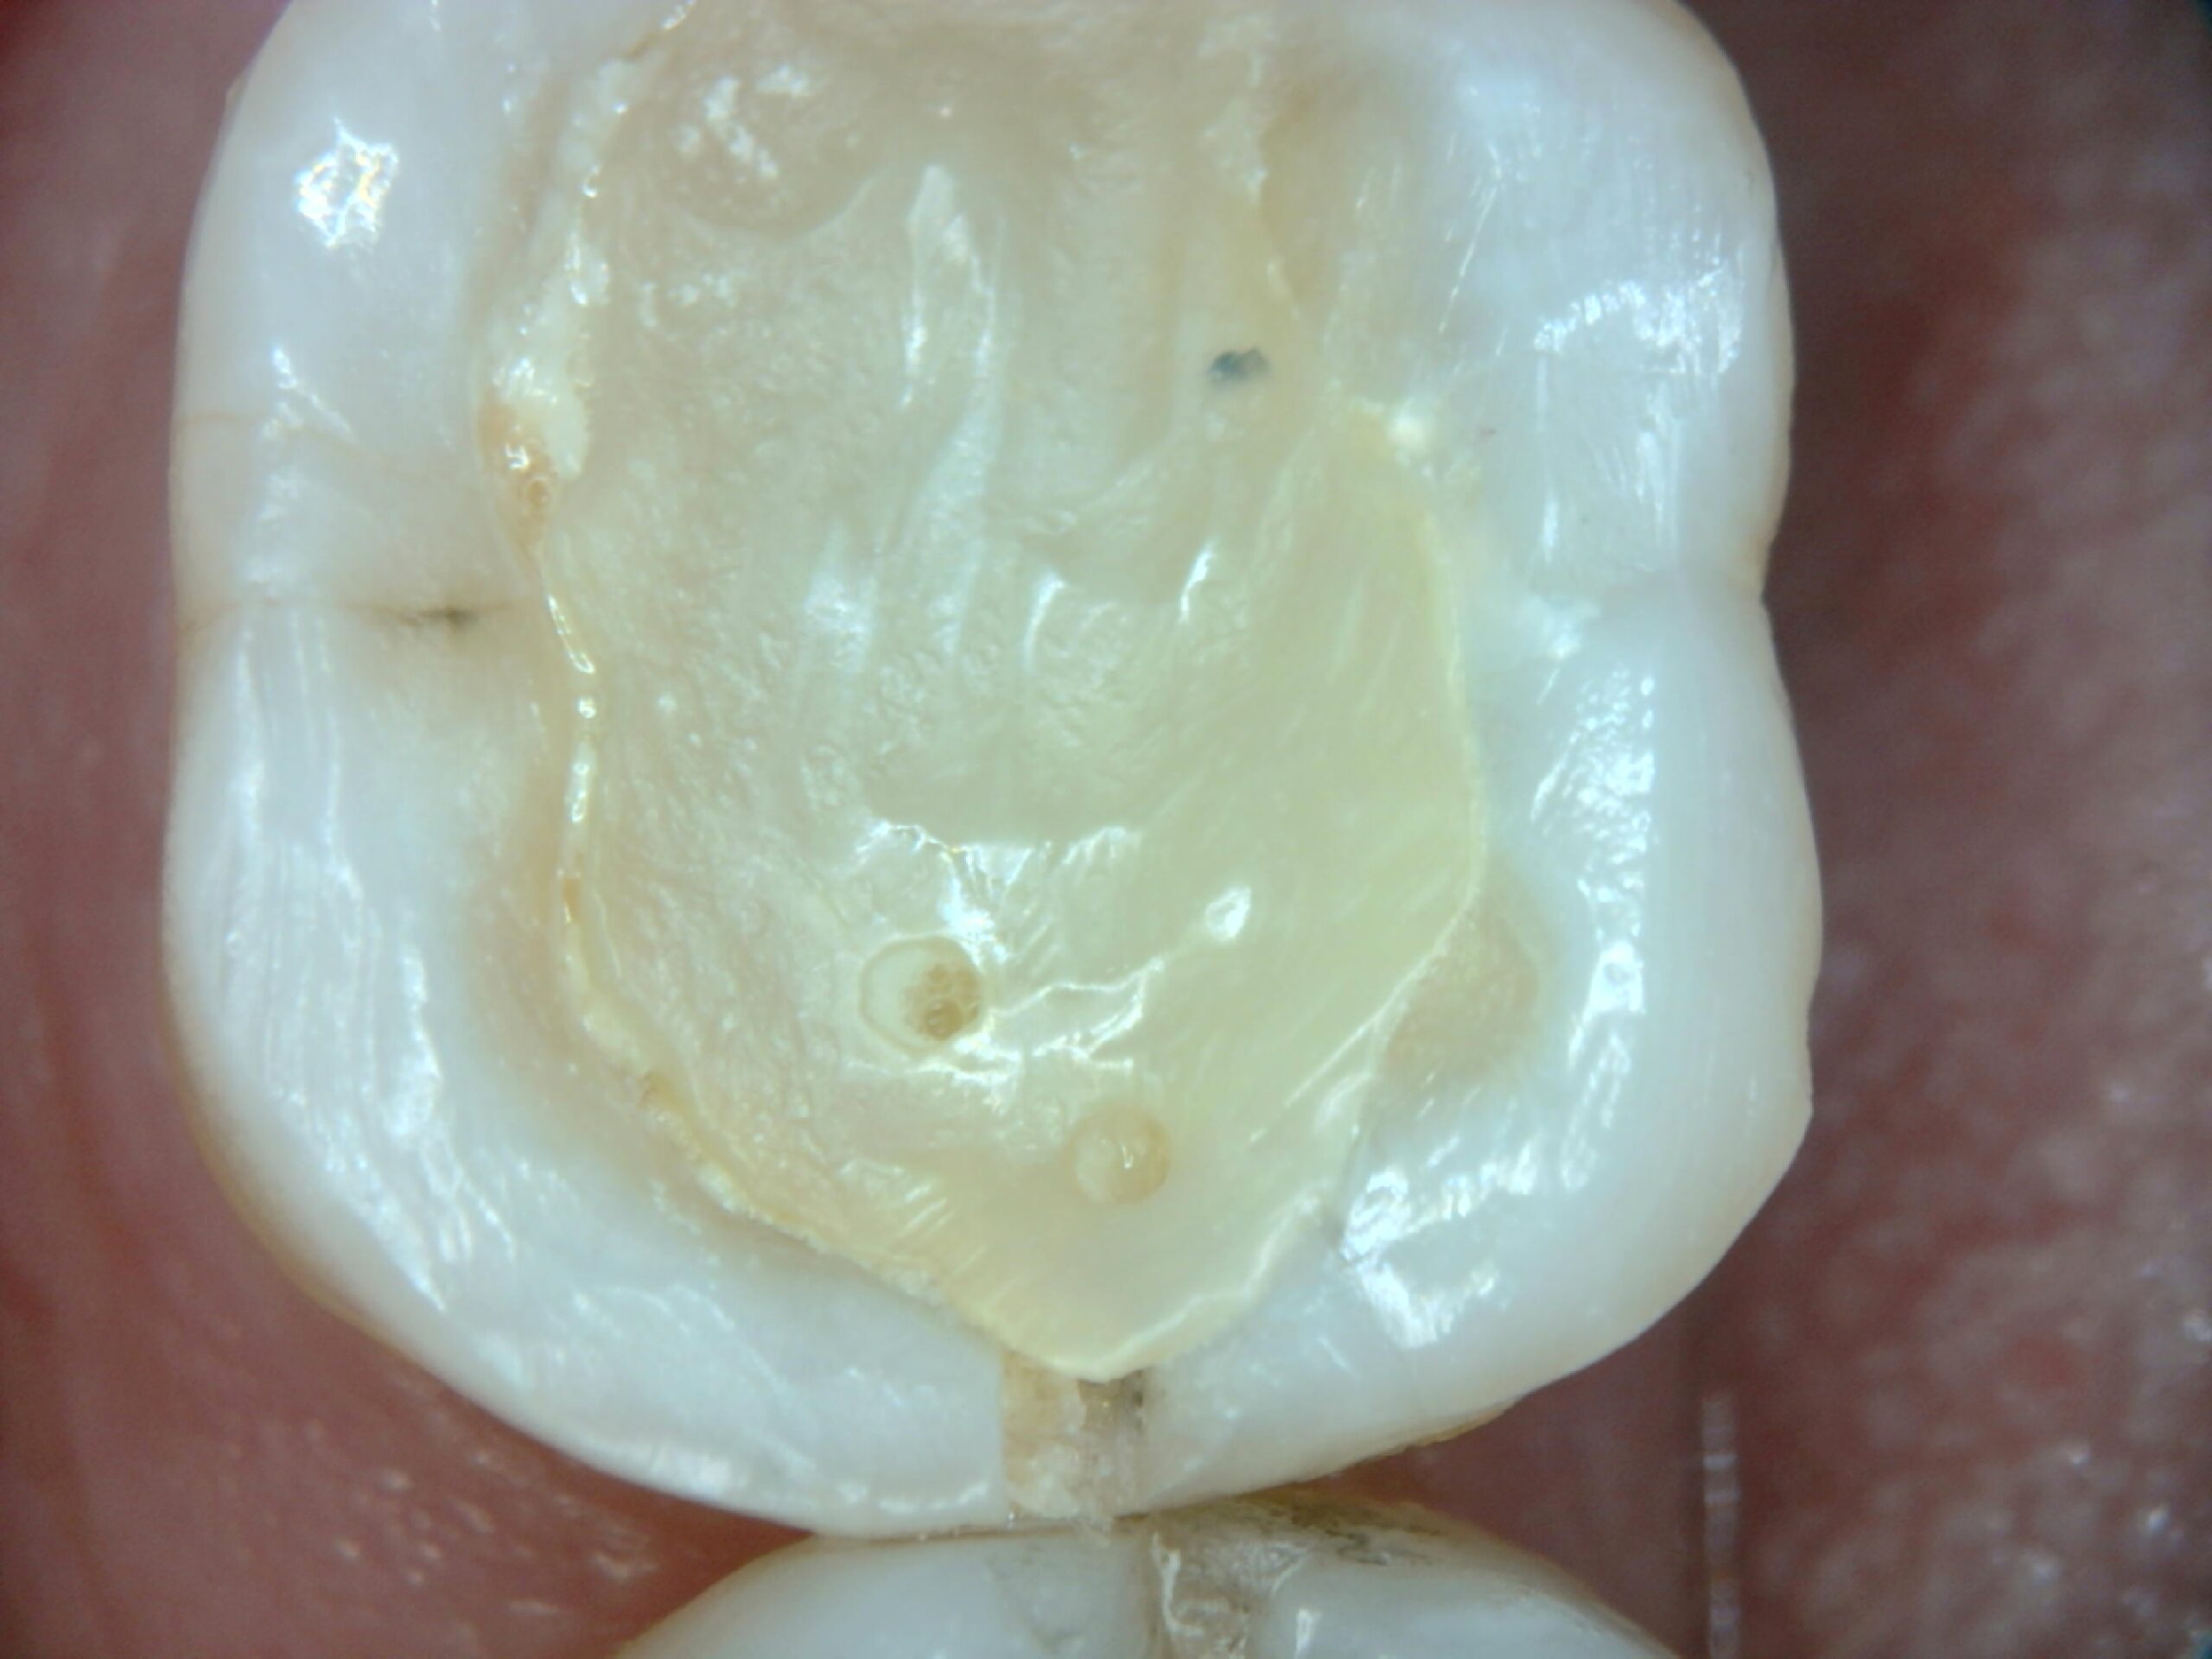

Trincas e microfraturas coronárias

Trincas, fraturas e infiltrações ficam extremamente evidentes com a ampliação da SkyCam.

Exemplos reais de uso da SkyCam na Endodontia